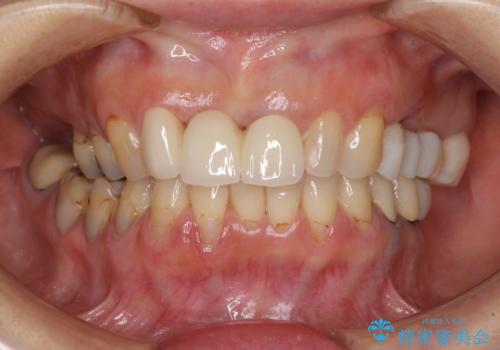

折れてしまった前歯 オールセラミックブリッジで自然な口元に

折れた前歯を抜歯すると、歯肉が痩せてしまい、ブリッジの形態の審美性が失われることがあります。仮歯を調整することで審美回復が必要であるか判断しますが、今回は歯肉移植を行うことなく補綴治療を行いました。